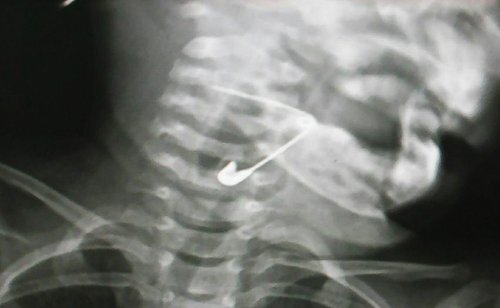

Bé 18 tháng tuổi nuốt kim băng mắc vào thanh quản

Trong lúc chơi đùa, bé gái ở Quảng Nam nuốt chiếc kim băng dài khoảng 3cm mắc trong hạ họng thanh quản.